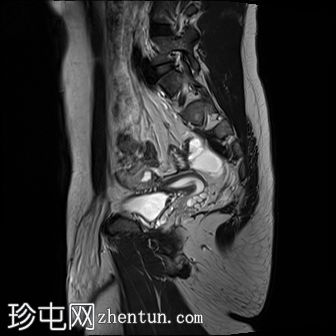

矢状位

T2

MRI图像显示子宫和睾丸。子宫内膜腔开口于前列腺尿道。

患者有双侧隐睾病史。CT和MRI图像显示发育良好的子宫和两个睾丸,均位于盆腔内。子宫内膜腔开口于前列腺尿道。

该患者表型为男性,阴茎发育良好。精液分析显示无精子症。结合影像学检查结果,最可能的诊断是持续性苗勒氏管综合征。这是一种男性假两性畸形,由子宫内抗苗勒氏管激素(AMH)分泌不足引起。AMH或其信号通路的缺乏导致苗勒氏管衍生结构的持续发育。

可通过核型分析(46XY)或盆腔性腺活检证实睾丸组织的存在来确诊。